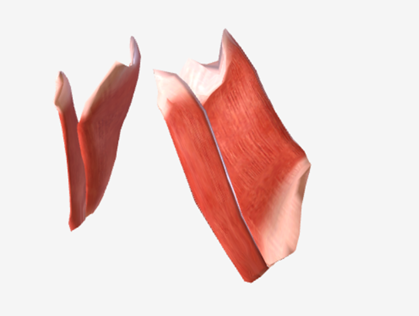

Medial pterygoid

origin is the medial pterygoid plate of the sphenoid bone, coursing down and back to the mandibular ramus; function is to elevate the mandible

Lateral pterygoid

origin is the lateral pterygoid plate and the greater wing of the sphenoid, coursing back to the mandible; function is to protrude the mandible